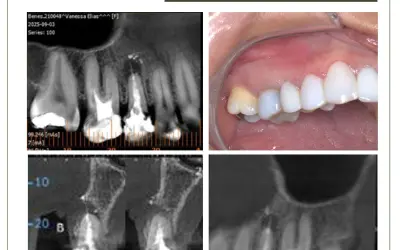

Paciente cirurgiã dentista, procurou a clínica pra retratamento de dente 11 com fístula, tratado há 3 anos e com um pino de fibra no interior do canal. Com a utilização de microscópio e pontas de ultrassom, o retentor foi ultrapassado e desgastado para o retratamento endodôntico do canal.

1.Radiografia inicial.

2.Análise e identificação dos seguintes elementos: pino, cimento, dente e resina.

6.O diâmetro das pontas de ultrassom deve ser compatível com o do canal em cada terço radicular. A realização de radiografias transoperatórias é fortemente recomendada.

8.Radiografia final.